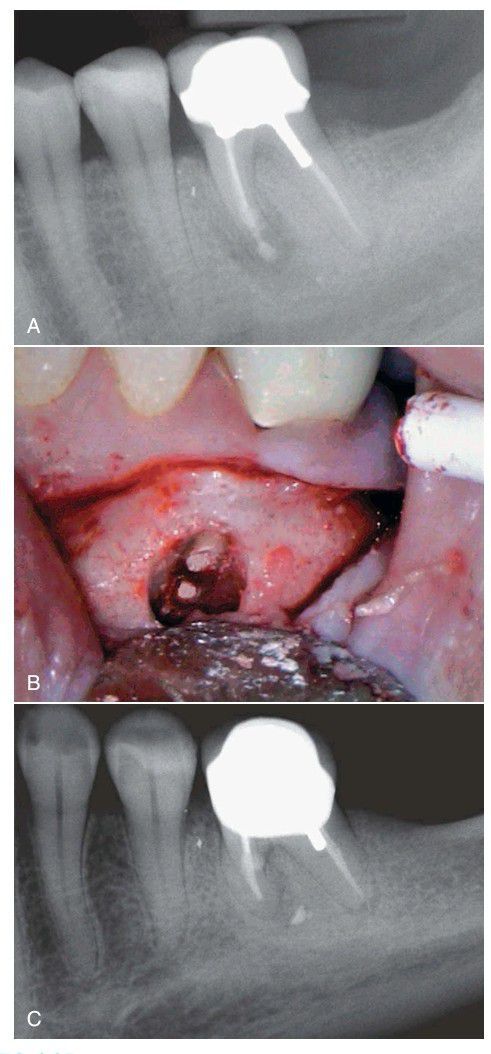

Pulp infections that are refractory to endodontic treatment may often result from vertical root fractures. A, This radiograph shows the placement of retrograde restorations in the apex of the mesial roots of this lower left first molar. B, This photograph shows that the restorations are directly in the root’s apex. C, After a little more than 1 year, the retrograde restorations are observed to have been dislodged, suggesting the possibility of a vertical root fracture.